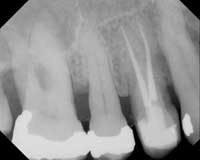

Predictable results build confidence. Such confidence improves the patient experience. What will help build this confidence and make endodontics more enjoyable for both patient and clinician? The Twisted File (TF) (SybronEndo, Orange, Calif.) is a huge step forward. Created from a proprietary process of heating, cooling and twisting nickel titanium, the file possesses dramatic cutting efficiency, and yet possesses far greater resistance to breakage from torsion and cyclic fatigue, empirically three to four times existing brands in my hands. Existing RNT systems are primarily ground, but grinding introduces microcracks into the finished metal. These microcracks can be the focus of fracture if the file is exposed to excessive torsion and cyclic fatigue. TF does not suffer from these limitations, as it is never machined across the grain structure of the metal aside from the qualities it possesses from the heating, cooling and twisting (Fig. 1).

TF is a revelation to use. It tracks canals well, moves apically without undue pressure, and with adequate irrigation and recapitulation it efficiently creates the desired shape of preparation. This efficiency safely creates reproducible results, making the patient experience more pleasant and the clinician more confident, a winning combination (Fig. 2).